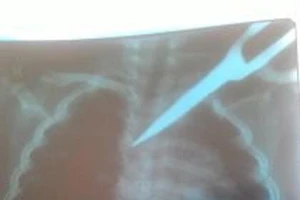

Cấp cứu kịp thời bé gái bị kéo đâm xuyên ngực